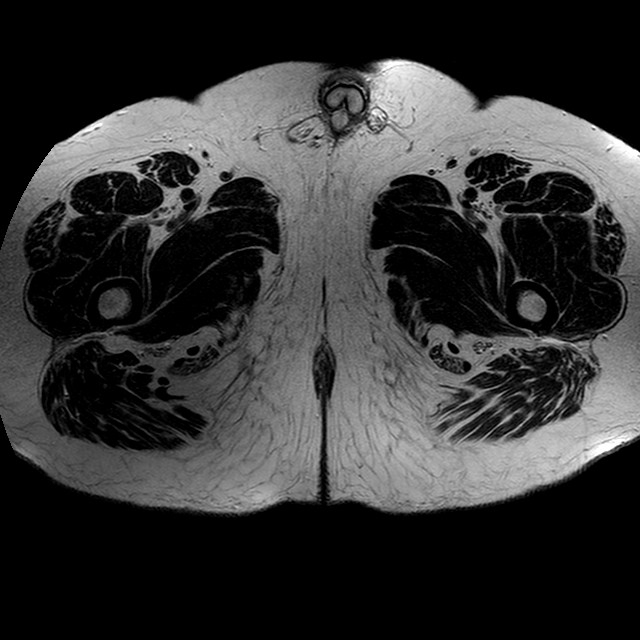

Esami: RMN BACINO

T2w TSE

Evidenti e simmetriche alterazioni osteofitosiche in regione coxo femorale con riduzione delle rime articolari. Degenerazione completa del cercine glenoideo. Non attuali segni di versamento articolare. Non segni di edema osseo che escludono attuale algodistrofia od osteonecrosi. Lieve e simmetrica riduzione del trofismo della muscolatura glutea.